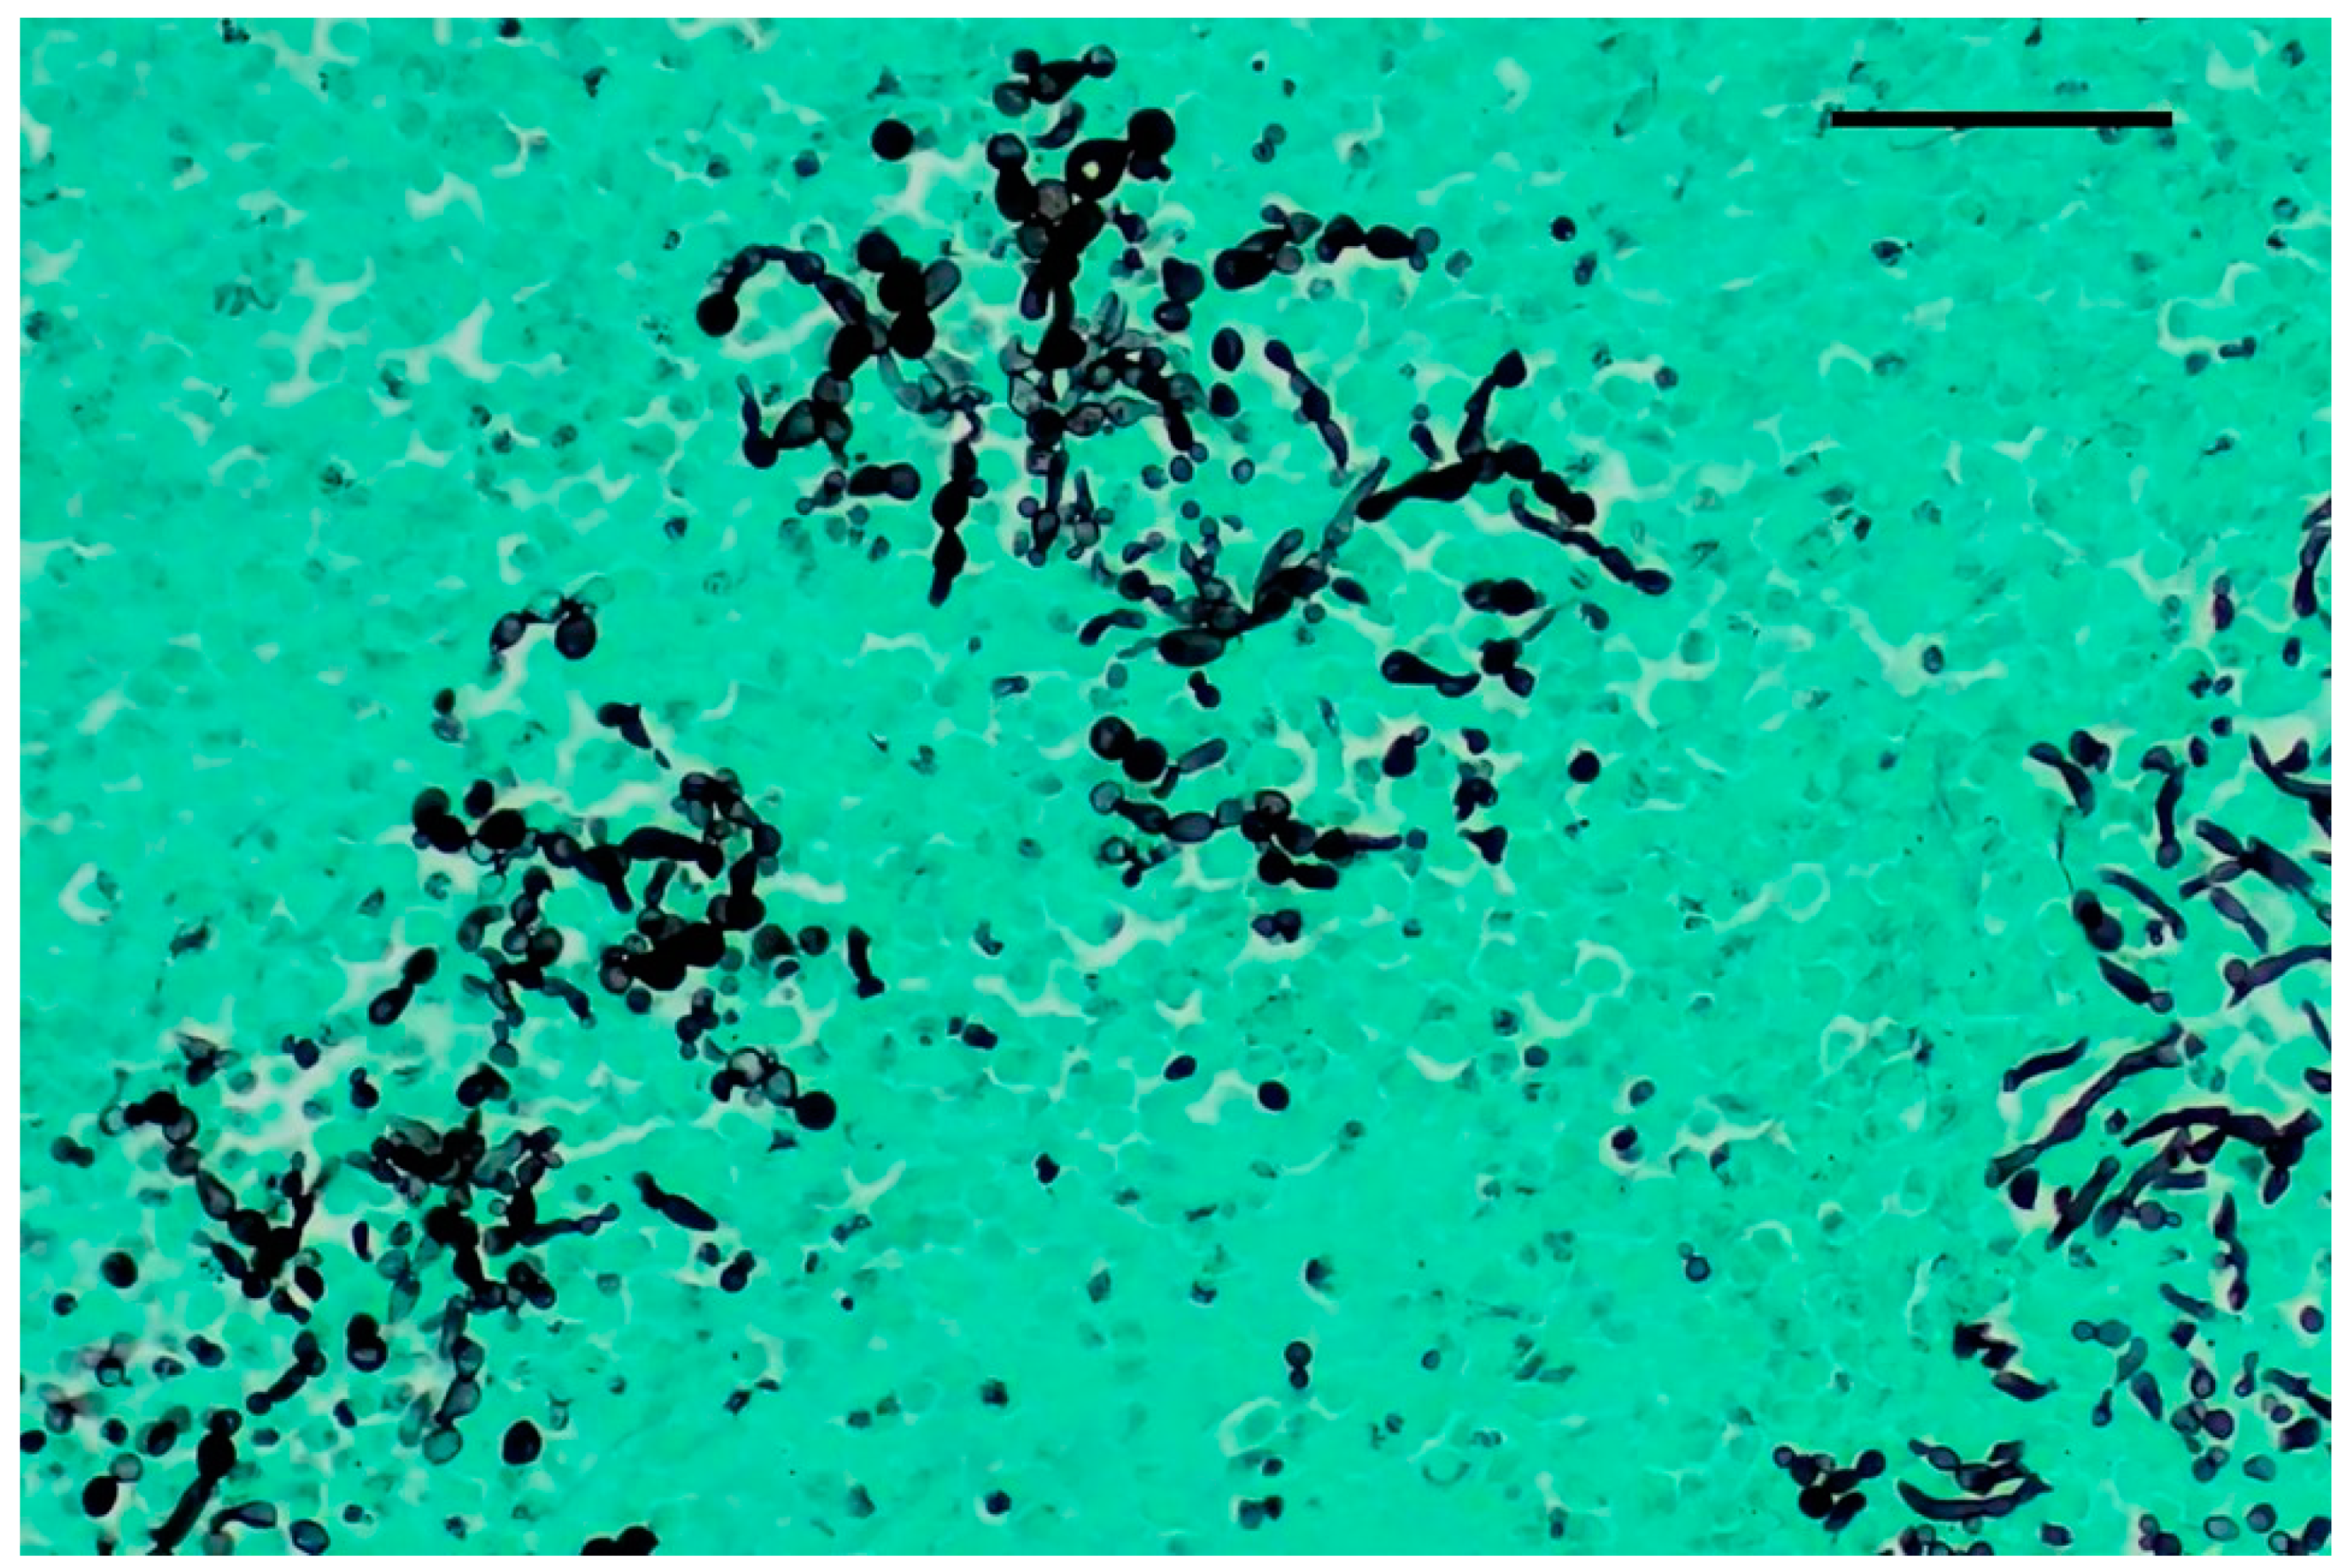

2.4. Cytological Examination